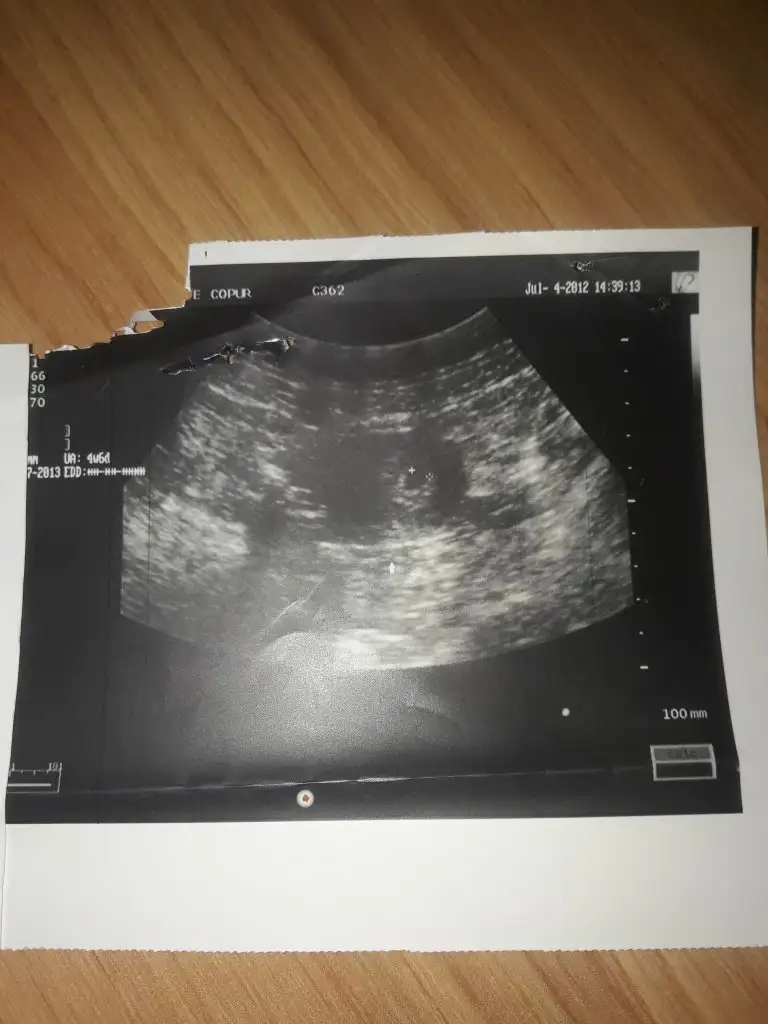

Normal usg ye gore sag ve sol ne oluyor kiz erkek olarak. Dogruluk payi ne kadar dogru anket yaptiniz mi bu konudaHimm bakalom normal usg de ne cokicak 3. Oglum olucak olursa

Karından usg sag kız sol erkekNormal usg ye gore sag ve sol ne oluyor kiz erkek olarak. Dogruluk payi ne kadar dogru anket yaptiniz mi bu konuda